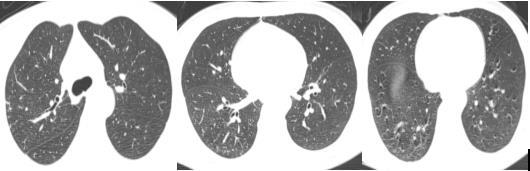

“患者转入我院时情况非常危急,出现发热、呼吸困难,生命体征不稳定。”肺病科专科主任柯佳副主任医师回忆道,“血液检查显示白细胞计数高达14.59×10⁹/L,C反应蛋白150.41mg/L,降钙素原0.24ng/ml,胸部CT显示肺部感染严重。”

令人欣喜的是,治疗一周后张先生炎症指标显著下降,10天后胸部CT显示肺炎明显好转,13天后成功拔除气管套管。后续通过系统的呼吸肌训练、吞咽功能训练等康复治疗,呼吸功能稳定,19天后顺利出院。

张先生入院治疗前胸部CT

张先生入院治疗后胸部CT